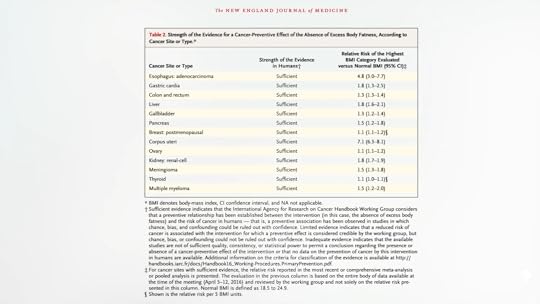

C is for Cancer. As many as three-quarters of people surveyed “were unaware that being overweight or obese increased a person’s risk of cancer,” when, in fact, based on a comprehensive review of more than a thousand studies, excess body fat raises the risk of most cancers, including esophageal, stomach, colorectal, liver, gallbladder, pancreatic, breast, uterine, ovarian, kidney, brain, thyroid, and bone marrow (multiple myeloma) cancers, as you can see below and at 2:00 in my video.